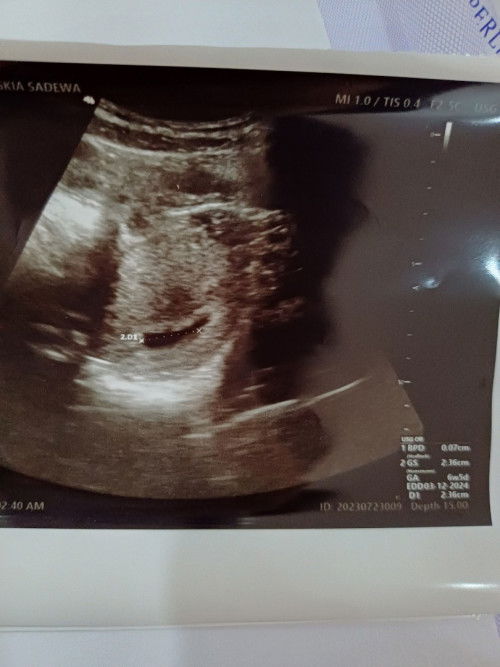

Kantung kehamilan tidak berbentuk bulat

Bunda, mau tanya siapa tau ada pencerahan atau informasi. Seminggu kemarin saya usg usianya 6w5d, baru terlihat kantungnya saja tapj bentuk kantungnya tidak bulat. Berbentuk lonjong seperti cabe, apakah normal bun? Yg saya lihat bentuk kantung biasanya bulat

6w1d saya gini bun